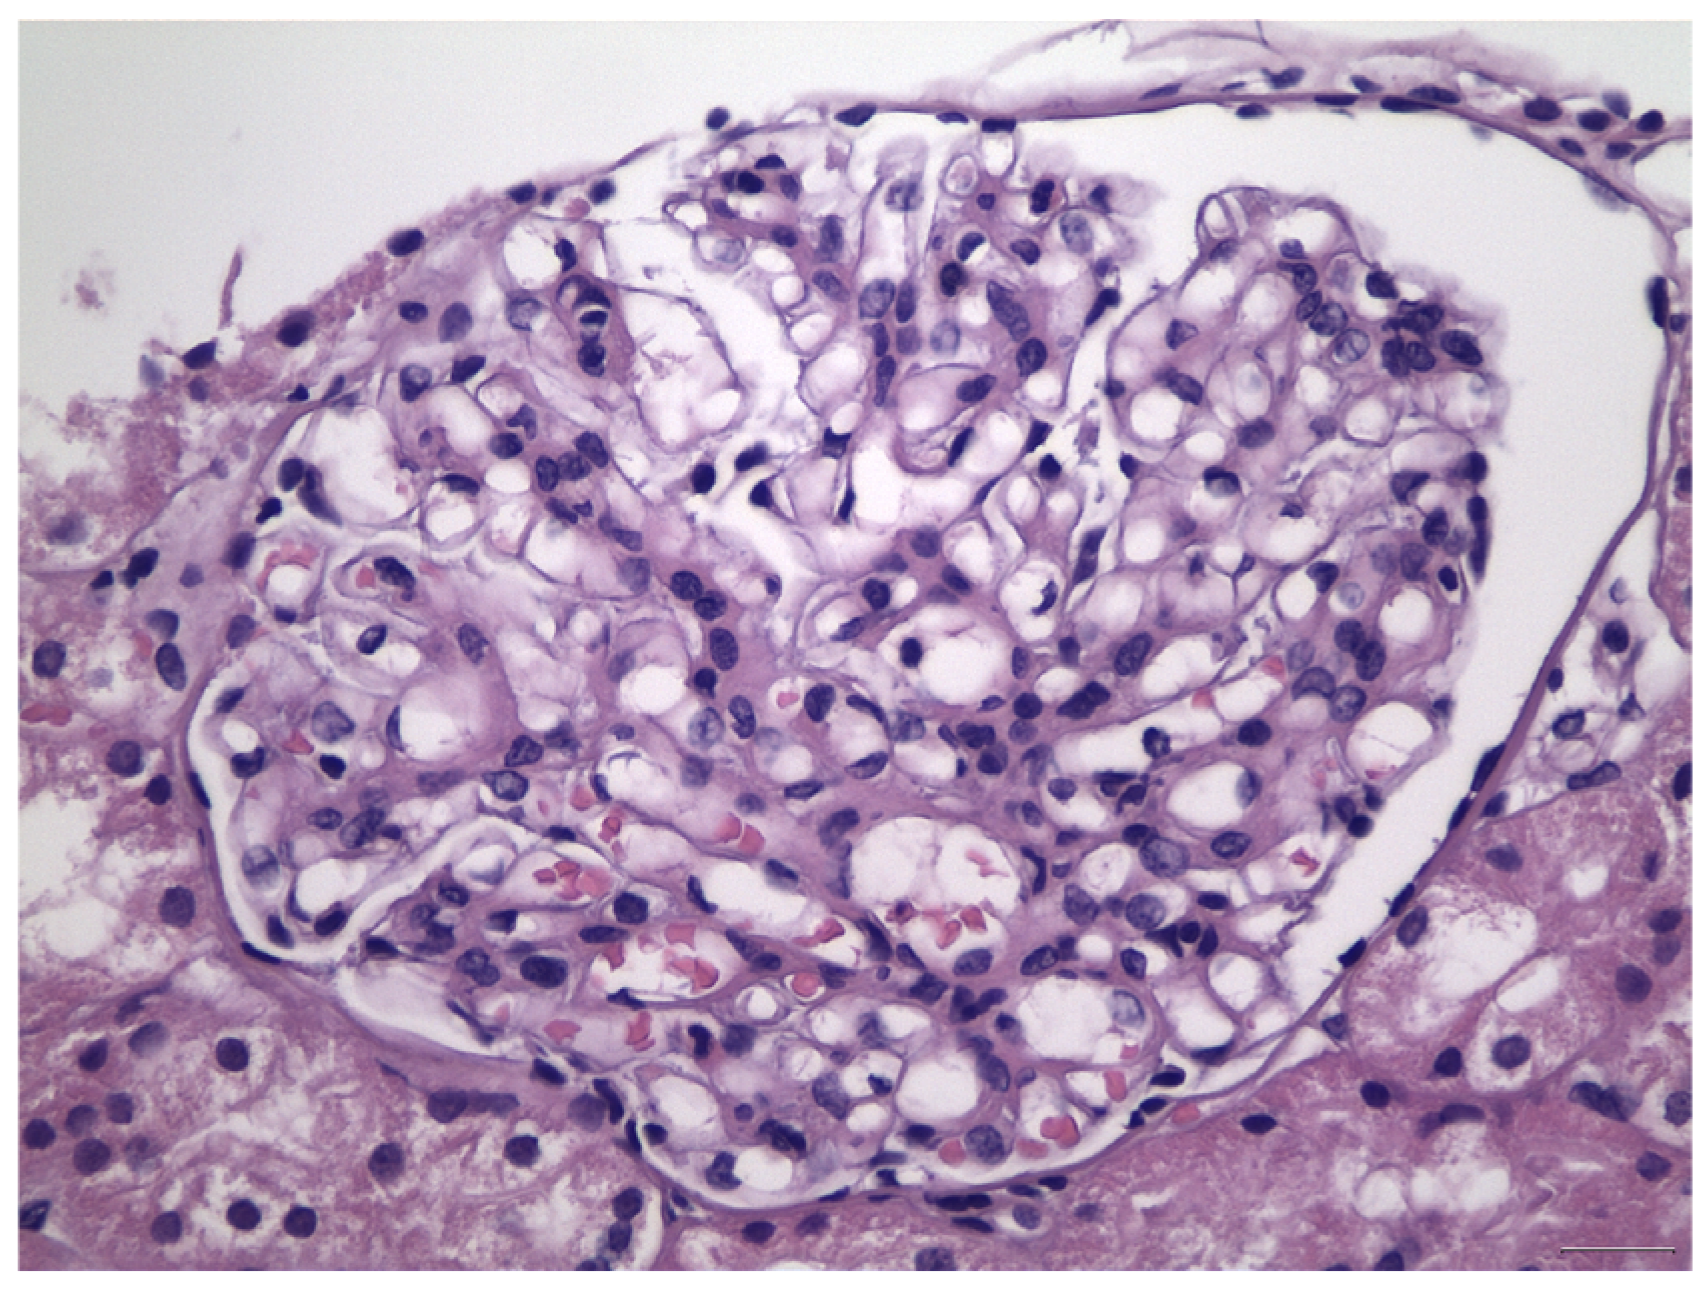

Histologically, IgAN is characterized by increase of the mesangial matrix and mesangial cell proliferation, as well as strong, dominant IgA deposition (≥2+), usually accompanied by C3 complement component, and/or IgG immunoglobulin in a lesser degree than IgA immunoglobulin and l light chain deposition, in Immunofluorescence examination. Although many cases show only mesangial proliferation, there are some cases that exhibited both mesangial and endocapillary proliferation with the influx of inflammatory cells into capillary lumens, or even extra-capillary proliferation, with glomerular crescents formation. Segmental glomerular sclerosis/scarring is also another relatively common feature, mimicking sometimes, focal segmental glomerulosclerosis, in cases showing signs of chronicity. Mesangial electron-dense deposits and a few small scattered subendothelial deposits are typically found in Electron Microscopy (EM) examination, although, in some cases, subendothelial deposits can be large. Rarely, a few small subepithelial deposits can also be recognized, although with no true membranous pattern. The tubulointerstitial department may show varying degrees of interstitial fibrosis or tubular atrophy, as well as red blood cell casts into tubular lumens. Thus, IgA nephropathy exhibits a wide spectrum of histological variability, ranging from no essential histological abnormalities to diffuse proliferative and crescentic glomerulonephritis, although most common histological patterns include focal or diffuse mesangial proliferative glomerulonephritis. Without treatment, some of the cases will progress to interstitial fibrosis and tubular atrophy, as well as glomerular scarring and loss, leading to end-stage renal disease. Taking into account the high histological diversity of the disease, but also clinical course variability, several histological grading schemes have been developed and proposed after Berger’s original disease description [12], in order to optimize therapeutic intervention and even to predict patients’ clinical course, among them, the Haas grade scheme is one of the most widely used [13]. The Oxford Classification grading scheme gained interest in the recent years and after Consensus meetings, the MEST-C score is highly recommended to be applied in every case [14,15]. In MEST-C (from Heptinstall’s Pathology of the kidney [16]), M0 or M1 indicate mesangial hypercellularity (≥4 cells in one or more mesangial areas) in ≤50% vs. >50% of glomeruli. E0 or E1 indicate endocapillary hypercellularity in zero vs. one or more glomeruli. S0 or S1 indicate segmental sclerosis in zero vs. one or more glomeruli. T0, T1, or T2 indicate tubular atrophy/interstitial fibrosis in ≤25%, 26% to 50%, or 50% of the renal cortex, respectively. C0 or C1 or C2, if cellular and/or fibrocellular crescents are absent, present in at least one glomerulus or at least 25 percent of glomeruli. Fibrous crescents are not counted toward this score (Figure 1, Figure 2, Figure 3 and Figure 4).

Figure 1.

Mild-to-moderate increase in mesangial matrix and mesangial cell proliferation in the case of IgA nephropathy, class M1E0S0T0, according to Oxford Classification.